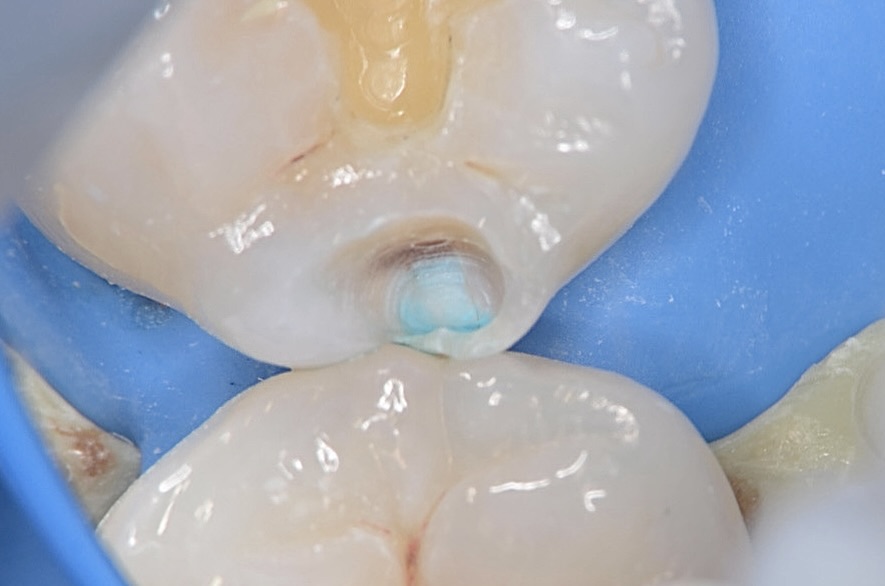

5番遠心

虫歯が齲蝕検知液で青く染まります。 -

虫歯除去

虫歯が齲蝕検知液で染まらなくなるまで削ると、結構な大きさの虫歯であったことがわかります。 -